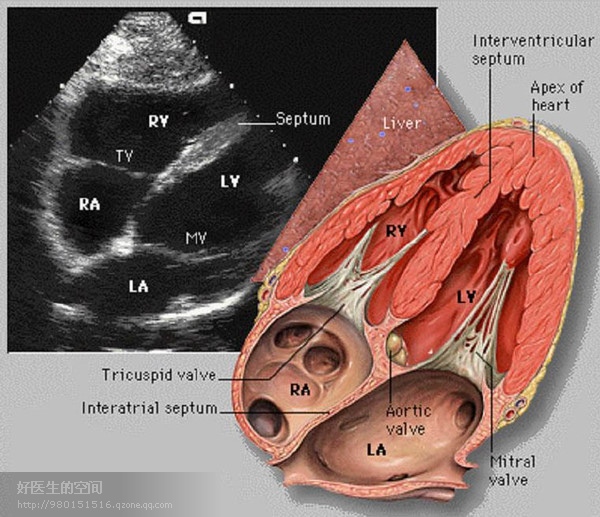

经典心脏超声切面图及解剖标示